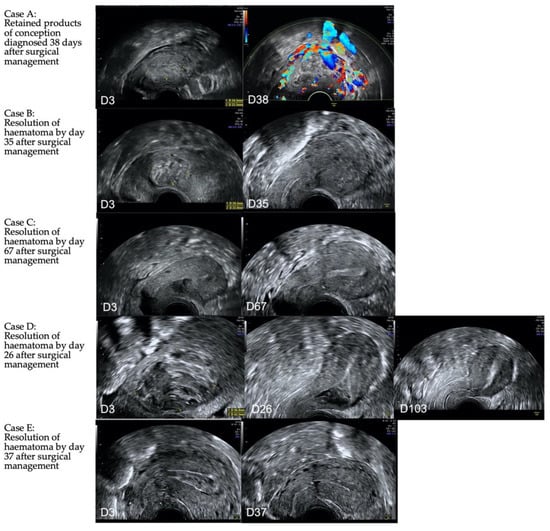

- If surgical management is performed, intraoperative transrectal ultrasound guidance is crucial to reduce the risk of retained tissue, bleeding and uterine perforation. Post operative intrauterine haematoma is common and can be difficult to differentiate from retained products of conception. Therefore, objective sonographic evidence of complete uterine evacuation at the time of the procedure improves postoperative investigation and diagnosis.

- Following surgical management, patients should have access to the clinical team due to the risk of ongoing bleeding and infection. A follow-up transvaginal ultrasound should be performed after 6 weeks, with anticipation of resolution of an intrauterine haematoma. At this assessment, the myometrial defect from CS should be assessed. In cases of recurrent CSP and a large myometrial defect, surgical repair of the defect can be discussed.